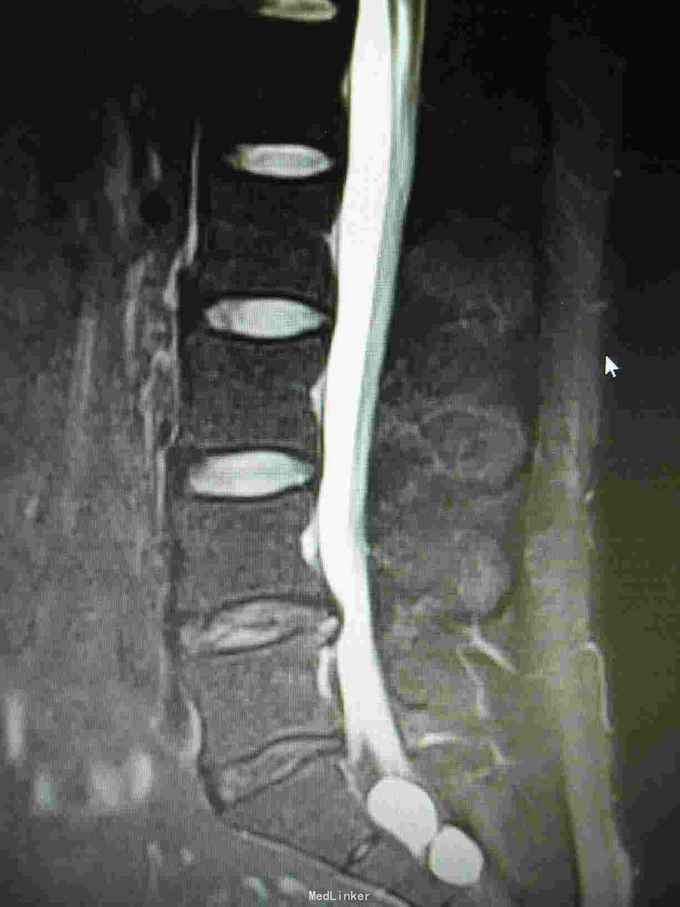

腰椎间盘突出 腰椎间盘突出症 骶管囊肿

29岁男性,腰腿疼5个月,加重1周,近一周疼痛向右臀及大腿放射至足底伴麻木。

步态正常,腰椎曲度变直,右侧跟腱反射未引出。右小腿外侧,右大腿后侧麻木,感觉减退

1:腰椎间盘突出症2:骶管囊肿

该患者L4/5椎间盘中央突出,L5/S1椎间盘向左突出。手术右侧L4/5,L5/S1开窗,见骶1神经根与骶管囊肿粘连,压迫变性,水肿,变粗硬化。